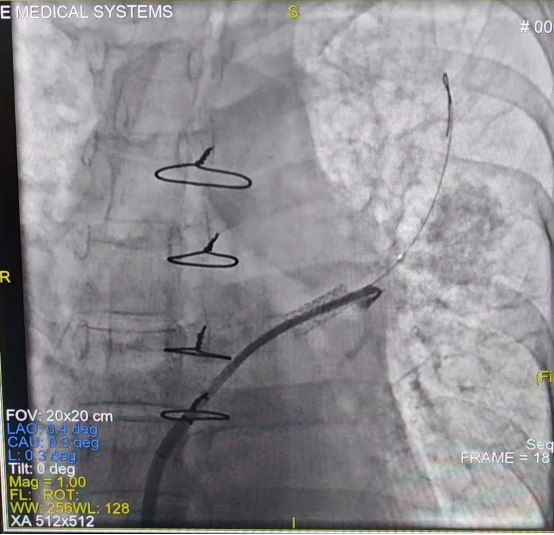

由于该手术难度极高(CMI值达17.8),心内一科与肺血管病与介入医学科联合为其制定周密手术方案。术前肺动静脉增强CT提示左肺动脉狭窄、左上、左下肺静脉闭塞,右上肺静脉狭窄。术中,心内一科尚粉青主任与孙杨医生行右心导管检查,明确其属于“毛细血管前肺动脉高压”。李积安主任、王鹏军副主任医师行经肺动脉间接肺静脉造影,再次证实左上、左下肺静脉闭塞,右上肺静脉狭窄。成功行房间隔穿刺,左肺肺静脉造影发现左上肺静脉完全闭塞,反复导丝尝试后成功开通了闭塞的肺静脉并行球囊扩张及支架植入,后再次行右肺静脉扩张,造影证实肺静脉回流正常,术后患者病情平稳,胸腔积液迅速吸收,症状明显改善,3天后胸腔积液完全消失。9月2日开学之际,李女士康复出院,终于能够回家照顾孩子,重归正常生活。

左上肺静脉开通成功进入真腔